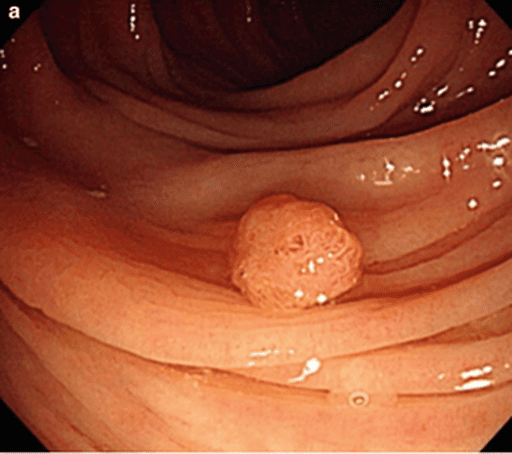

At the organ level, editing difficulty varies significantly. Regions such as the spine and bones (e.g., CT scans) remain especially challenging, with the best EA only reaching 0.38. This difficulty is not primarily due to grayscale input but rather the inherent structural complexity of bones. Unlike soft tissues, bones follow rigid, geometrically consistent patterns (e.g., aligned vertebrae, symmetric ribs), making even small editing errors visually salient and disruptive. For example, in a task like “correct spines”, the model must straighten the spine without disturbing rib symmetry or vertebral alignment, demanding a much higher degree of structural precision than tasks such as “remove intestinal polyps”. The largest performance gaps between Gemini and open-source models are seen in teeth (34%), hands (64%), and gastrointestinal tract (43%), further reflecting the challenges posed by complex anatomical structures and repetitive patterns. Conversely, superficial structures such as hair and nose are easier to edit, where ICEdit achieves strong performance (hair: EA = 0.71, VQ = 0.79).

Three key observations arise: (1) Internal organs are significantly harder to edit than superficial structures, with EA scores averaging 2.3 lower; (2) Gemini’s advantage is most pronounced in anatomically complex regions with repetitive patterns (e.g., hands, gastrointestinal tract); and (3) A trade-off exists between visual quality and context preservation: models with higher VQ, such as Gemini, tend to exhibit slightly lower CP, highlighting the need for localized, precise edits rather than full-image redraws in medical applications.

| Previous | Truth | Gemini2 | SeedX | Imagic | IP2P | InstructDiff. | PaintByInpaint | ICEdit |

| Remove intestinal polyps. | 0.8/0.8/0.8 | 0.2/0.3/0.2 | 0.2/0.7/0.5 | 0.3/0.7/0.8 | 0.1/0.5/0.7 | 0.0/0.3/0.3 | 0.2/0.6/0.7 | |

| Remove intestinal adenoma. | 0.8/0.6/0.9 | 0.7/0.7/0.7 | 0.2/0.5/0.3 | 0.0/0.6/0.8 | 0.0/0.3/0.2 | 0.0/0.4/0.5 | 0.0/1.0/0.9 | |